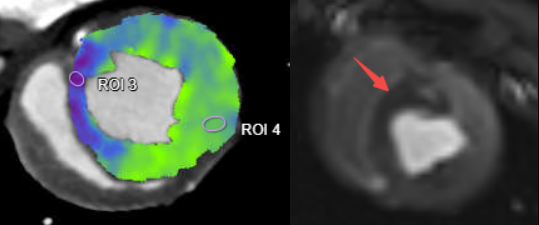

uCT SiriuX落地临床验证中,我们切身体会了这款设备的全脏器覆盖能谱成像功能,可在单心动周期内完成全心能谱采集,提供多种能谱图像类型。

例如,虚拟单能图像可优化冠脉图像对比度,有效消除血管管腔中钙化导致的晕状伪影,确保准确的血管评估;同时,基于能谱图像的物质识别技术,还可进行斑块成分分析,进一步提升诊断精度。

CT心肌灌注 VS MR心肌灌注

CT心肌延迟显像 VS MR ECV(心肌细胞外容积)

此外,通过心脏能谱成像的虚拟高能图像,系统能够有效抑制严重钙化和支架场景下的伪影。在心肌灌注成像的基础上,结合能谱成像的碘定量分析,有望解决CT值差异带来的灌注参数标准化难题,进一步提高诊断精度。